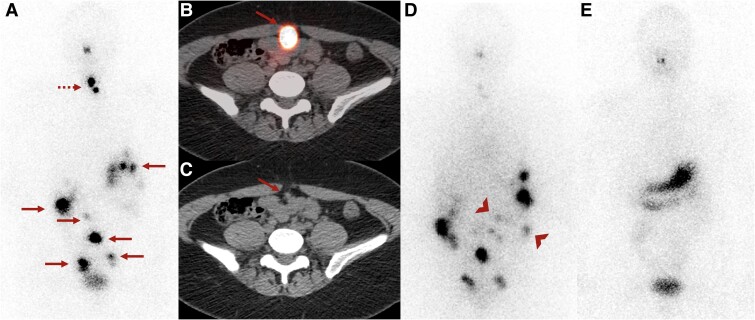

Struma ovarii (SO) is a rare subtype of ovarian teratoma composed of more than 50% thyroid tissue. Extraovarian spread of SO, called peritoneal strumosis, was previously considered benign given the lack of histological malignant features. However, the 2020 World Health Organization Classification of Female Genital Tumors reclassified peritoneal strumosis as highly differentiated follicular carcinoma of ovarian origin (HDFCO), highlighting its low-grade malignant potential. We present a 38-year-old woman with SO treated initially with right salpingo-oophorectomy, with recurrence 2 years later with multifocal metastatic lesions in the abdomen and pelvis that was successfully treated with surgical resection, total thyroidectomy, and 157 mCi of I-131. Tumor molecular testing revealed a pathogenic DICER1 variant (c.5428G>T, exon 25). A second variant (c.319delins13, exon 4) was of uncertain significance. Germline testing confirmed the second DICER1 variant and also identified an increased risk variant in the APC gene (c.3920T>A). This is a rare case of extensive HFDCO with DICER1 variants, which has been associated with thyroid cancer. Given the germline DICER1 variant, this may also represent the first reported instance of DICER1 syndrome manifesting as HDFCO. Further research into the prognostic factors and optimal treatment of HFDCO is needed.